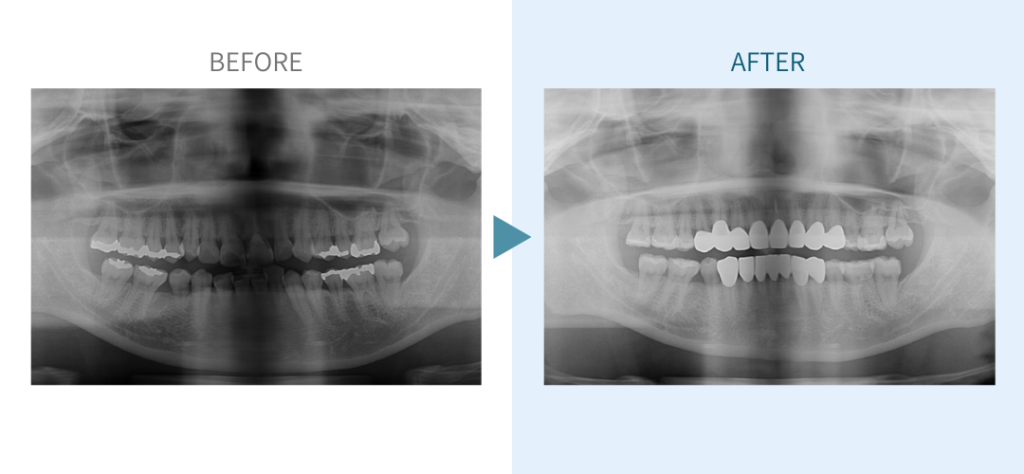

デンタルチームジャパンでは、サイナスリフト(上顎洞底挙上術)や骨造成など、他院で「骨が足りない」と断られた難症例にも対応しています。

私たちは、難症例に関する治療法を学会でも発表しており、その豊富な実績と技術力が評価され、全国から患者様が来院いただいております。

こちらではその一部の症例についてご紹介します。